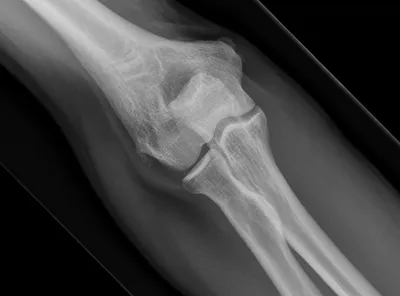

Supracondylar fracture of elbow

Elbow

4/10/2026